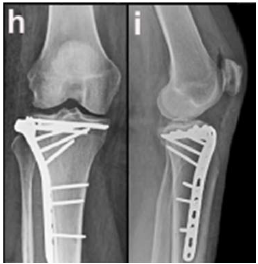

A respeito da técnica empregada na osteossíntese do platô tibial nesse caso, é correto afirmar que a placa lateral

A abordagem cirúrgica para a osteossíntese foi realizada pela via

Assinale a alternativa que indica os princípios a serem seguidos na osteossíntese do platô tibial lateral, nesse caso.

No acesso cirúrgico para o caso, deve-se abordar a articulação do joelho através do espaço entre os músculos